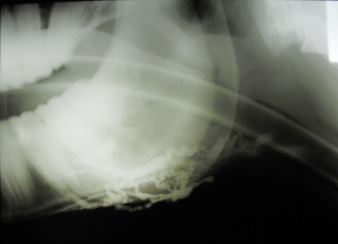

Fig. 2. A 20-G intravenous catheter placed into the right congestive facial vein in the anesthetized horse. The left jugular vein appeared as an anechoic tubular structure which collapsed under the probe pressure, the color Doppler examination revealed normal blood flow within the vessel (Fig. 3). Bi-dimensional ultrasonography of the right jugular vein showed a heterogeneous, non-cavitating, hypoechoic structure occluding a narrowed right jugular vein for about 30 cm of length localized in the proximal and mid-portion of the neck compatible with a thrombus (Fig. 4). The color Doppler examination showed blood flow through the lateral portions of the thrombus in the cranial and mid-portions of the right jugular vein (Fig. 5). Cranially to the thrombus, a marked distension of the maxillary and linguofacial veins was evident, with a turbulent and echogenic flow; the latter was compatible with blood stasis near the thrombus (Fig. 6). Caudally to the thrombus, the right jugular vein presented reduced diameter, thickened walls, and normal blood flow (Fig. 7). The cranial part of the thrombus originated from a heterogeneous scare tissue, localized at the level of the right mandibular angle (Fig. 8). After injection of the first saline contrast bolus in a right facial vein, no microbubbles appeared in the right jugular vein, caudally to the thrombus, proving the presence of a complete right jugular vein occlusion. On the contrary, after injection of the second bolus, microbubbles were visualized in the left jugular vein as small, intense, echo signals within the vein lumen, demonstrating the presence of collateral circulation that drained the blood from the right facial veins to the left jugular vein (Fig. 9). Venography results confirmed the complete occlusion of the right jugular vein and the presence of submandibular venous collaterals that connected the right facial veins with the left jugular vein (Figs. 10 and 11). Based on the previous results, the diagnosis of JVT with complete occlusion of the vessel lumen was confirmed. The horse’s owner refused any proposed medical or surgical therapy.

Fig. 10. Venographic examination, latero-lateral view. Note the large number of collateral vessels draining the contrast.

Fig. 11. Venographic examination, ventro-dorsal view. Note the large number of collateral vessels draining the contrast. Saline agitated microbubbles are small air-filled microspheres that have specific acoustic properties that make them useful as a contrast agent in ultrasound imaging. The microbubbles can be easily identified by a two-dimensional ultrasonography as they appear as small hyperechoic particles passing in the lumen of the vessel. Agitated saline solution is demonstrated to be safe in both large and small animals (Bonagura and Pipers, 1983). Air microbubbles disappear in a few seconds after intravenous injection; firstly, because the solubility of air in blood is high and, secondly, because the lungs filter the large microbubbles present in the agitated saline solution (Dijkmans et al., 2004). Jugular vein occlusion, secondary to thrombophlebitis and thrombosis, is one of the most common vascular diseases in horses. The condition is usually secondary to prolonged or improper placement of intravenous catheters or injections of irritating drugs that lead to mechanical or chemical injury of the vessel walls (Dickson et al., 1990; Spurlock et al., 1990; Meister et al., 1993; Schoster, 2017). In the clinical case described in this report, a repeated trauma due to a rope tied too tight around the neck may have caused abrasions at first, with a consequent deep subcutaneous fibrosis around the venous jugular wall, and consequently thrombosis. Other authors have previously reported a case of JVTP secondary to the extension of a buccal lesion in a thoroughbred horse (Matsuda et al., 2010). Although a previous study has shown that racing performances were only slightly negatively affected by JVTP in horses (Moreau and Lavoie, 2009), jugular vein occlusion may potentially decrease the athletic performances because of impaired venous drainage of the head that can lead to brain congestion and edema as well as nasal, pharyngeal, or laryngeal mucosal congestion that could potentially cause airway obstruction during intense exercise (Moreau and Lavoie, 2009). Because of that, several medical and/or surgical therapies have been proposed to recanalize the occluded vessel and reduce proximal venous congestion. In this context, SCU could therefore be used as a tool to monitor the effectiveness of therapy and the progression of the disease. The test can be performed in sedated animals, although, in our case, we put the horse under general anesthesia because he was going to be operated. One of the main limitations of the SCU test, in jugular vein occlusion, is that it is not able to distinguish between recanalization and homolateral compensatory circulation which drains the blood from the distal to the proximal area of the thrombus. This compensatory vascular pattern has been described in experimentally induced JVTP (Borghesan et al., 2018). In the clinical case described here, we did not observe the presence of collateral vessels that joined the cranial with the caudal extremities of the thrombus. We hypothesize that this type of collateral circulation develops only in experimentally induced JVTP due to the rapidity of the occlusion process. In conclusion, the SCU test appears as a valid method to assess the vessel patency in JVT in horses. The test could be used as a method to monitor the progression of the disease and the effectiveness of the therapy. Further studies are needed to evaluate the validity of SCU on horses with naturally occurring JVTP. AcknowledgmentsThe authors would like to thank Dr. Elizabeth Vargiu and Dr. Riccardo James Vargiu for English language editing of the manuscript and Miss Rita Fenu, the Radiology Technician of the Veterinary Teaching Hospital of the University of Sassari, for her valuable technical support. Conflict of interestThe authors declare that there is no conflict of interest. Authors’ contributionsAndrea Corda conceived and performed the procedure, drafted and revised the manuscript, and approved the final version. Nicolò Columbano conceived and performed the procedure, drafted and revised the manuscript, and approved the final version. Valentina Secchi performed the procedure, and drafted and revised the manuscript. Antonio Scanu performed the procedure, and drafted and revised the manuscript. Maria Luisa Pinna Parpaglia drafted and revised the manuscript. Giovanni Mario Careddu performed the procedure, drafted and revised the manuscript. Eraldo Sanna Passino performed the procedure, drafted and revised the manuscript, and approved the final version. ReferencesBäumer, W., Herrling, G.M. and Feige, K. 2013. Pharmacokinetics and thrombolytic effects of the recombinant tissue-type plasminogen activator in horses. BMC Vet. Res. 9, 158. Bonagura, J.D. and Pipers, F.S. 1983. Diagnosis of cardiac lesions by contrast echocardiography. J. Am. Vet. Med. Assoc. 182, 396–402. Borghesan, A.C., Barbosa, R.G., Cerqueira, N.F., Takahira, R.K., Vulcano, L.C., Alves, A.L.G, Watanabe, M.J., Alonso, J.M., Rollo, H.A. and Hussni, C.A. 2018. Evaluation of experimental jugular thrombophlebitis in horses treated with heparin. J. Equine Vet. Sci. 69, 59–65. Dallap, S.B.L. and Epstein, K. 2009. Coagulopathy of the critically ill equine patient. J. Vet. Emerg. Crit. Care (San Antonio) 19, 53–65. des Lions, J.A., Carette, O., de Broucker, C.-A., Tainturier, B. and Ribot, X. 2008. Utilisation de la streptokinase dans le traitement des thrombophlébites de la jugulaire chez le cheval: à propos de 2 cas cliniques. Bull la Société Vétérinaire Prat Fr. 92, 17–22. Dickson, L.R., Badcoe, L.M., Burbidge, H. and Kannegieter, N.J. 1990. Jugular thrombophlebitis resulting from an anaesthetic induction technique in the horse. Equine Vet. J. 22, 177–179. Dijkmans, P.A., Juffermans, L.J.M., Musters, R.J.P., van Wamel, A., Ten Cate, F.J., van Gilst, W., Visser, C.A., de Jong, N. and Kamp, O. 2004. Microbubbles and ultrasound: from diagnosis to therapy. Eur. J. Echocardiogr. 5, 245–256. Dolente, B.A., Beech, J., Lindborg, S. and Smith, G. 2005. Evaluation of risk factors for development of catheter-associated jugular thrombophlebitis in horses: 50 cases (1993-1998). J. Am. Vet. Med. Assoc. 227, 1134–1141. Epstein, K.L. 2014. Coagulopathies in horses. Vet. Clin. North Am. Equine Pract. 30(2), 437–452. Feige, K., Schwarzwald, C.C. and Bombeli, T. 2003. Comparison of unfractioned and low molecular weight heparin for prophylaxis of coagulopathies in 52 horses with colic: a randomised double-blind clinical trial. Equine Vet. J. 35, 506–513. Gardner, S.Y., Reef, V.B. and Spencer, P.A. 1991. Ultrasonographic evaluation of horses with thrombophlebitis of the jugular vein: 46 cases (1985-1988). J. Am. Vet. Med. Assoc. 199, 370–373. Gómez-Ochoa, P., Llabrés-Díaz, F., Ruiz, S., Corda, A., Prieto, S., Sosa, I., Gregori, T. and Gascon, M. 2010. Ultrasonographic appearance of the intravascular transit of agitated saline in normal dogs following ultrasound guided percutaneous splenic injection. Vet. Radiol. Ultrasound. 51, 523–526. Hussni, C.A., Barbosa, R.G., Borghesan, A.C., Rollo, H.A., Alves, A.L.G., Watanabe, M.J., de Vasconcelos Machando, A.M. and Cerqueira, N.F. 2012. Aspectos clínicos, ultrasonográfiicos e venográfiicos da trombo flebite jugular experimental em equinos. Pesqui. Vet. Bras. 32, 595–600. Hussni, C.A., Dornbusch, P.T., Garcia Alves, A.L., Thomassian, A., De Mello Nicoletti, J.L., Pantano De Cillo, G. and Vulcano, L.C. 2006. Avaliacao clinica e angiografica da vascularizacao consecutiva a resseccao experimental da jugular de equinos. Vet. e Zootec. 13, 163–168. Hussni, C.A., Dornbusch, P.T., Yoshida, W.B., Alves, A.L.G., Nicoletti, J.L.M., Mamprim, M.J. and Vulcano, L.C. 2009. Trombectomia com cateter de Fogarty no tratamento da tromboflebite jugular experimental em eqüinos. Pesqui. Vet. Bras. 29, 45–51. Matsuda, K., Suzuki, H., Tsunoda, N. and Taniyama, H. 2010. Jugular thrombophlebitis developed from buccal ulcer in a thoroughbred horse. J. Vet. Med. Sci. 72, 913-915. Meister, D., Fürst, A., Kaegi, B., Struchen, C., Kaser-Hotz, B. and Flückiger, M. 1993. Experiences with long-term intravenous therapy using teflon catheters in 80 horses. Tierarztl. Prax. 21, 437–443. Moreau, P. and Lavoie, J.P. 2009. Evaluation of athletic performance in horses with jugular vein thrombophlebitis: 91 cases (1988-2005). J. Am. Vet. Med. Assoc. 235, 1073–1078. Pentelado, M.D.D. and Correa, L.J. 2013. Jugular thrombophlebitis in horses: a reviw of fibrinolysis, thrombus formation, and clinical managment. Can. Vet. J. 54, 65–71. Rijkenhuizen, A.B.M. and Van Swieten, H.A. 1998. Reconstruction of the jugular vein in horses with post thrombophlebitis stenosis using saphenous vein graft. Equine Vet. J. 30, 236–239. Russell, T.M., Kearney, C. and Pollock, P.J. 2010. Surgical treatment of septic jugular thrombophlebitis in nine horses. Vet. Surg. 39, 627–630. Schoster, A. 2017. Complications of intravenous catheterization in horses. Schweiz. Arch. Tierheilkd. 159, 477–485. Schwarzwald, C.C., Feige, K., Wunderli-Allenspach, H. and Braun, U. 2002. Comparison of pharmacokinetic variables for two low-molecular-weight heparins after subcutaneous administration of a single dose to horses. Am. J. Vet. Res. 63, 868–873. Spurlock, S.L., Spurlock, G.H., Parker, G. and Ward, M.V. 1990. Long-term jugular vein catheterization in horses. J. Am. Vet. Med. Assoc. 196, 425–430. Wiemer, P., Gruys, E. and van Hoeck, B. 2005. A study of seven different types of grafts for jugular vein transplantation in the horse. Res. Vet. Sci. 79, 211–217. | ||